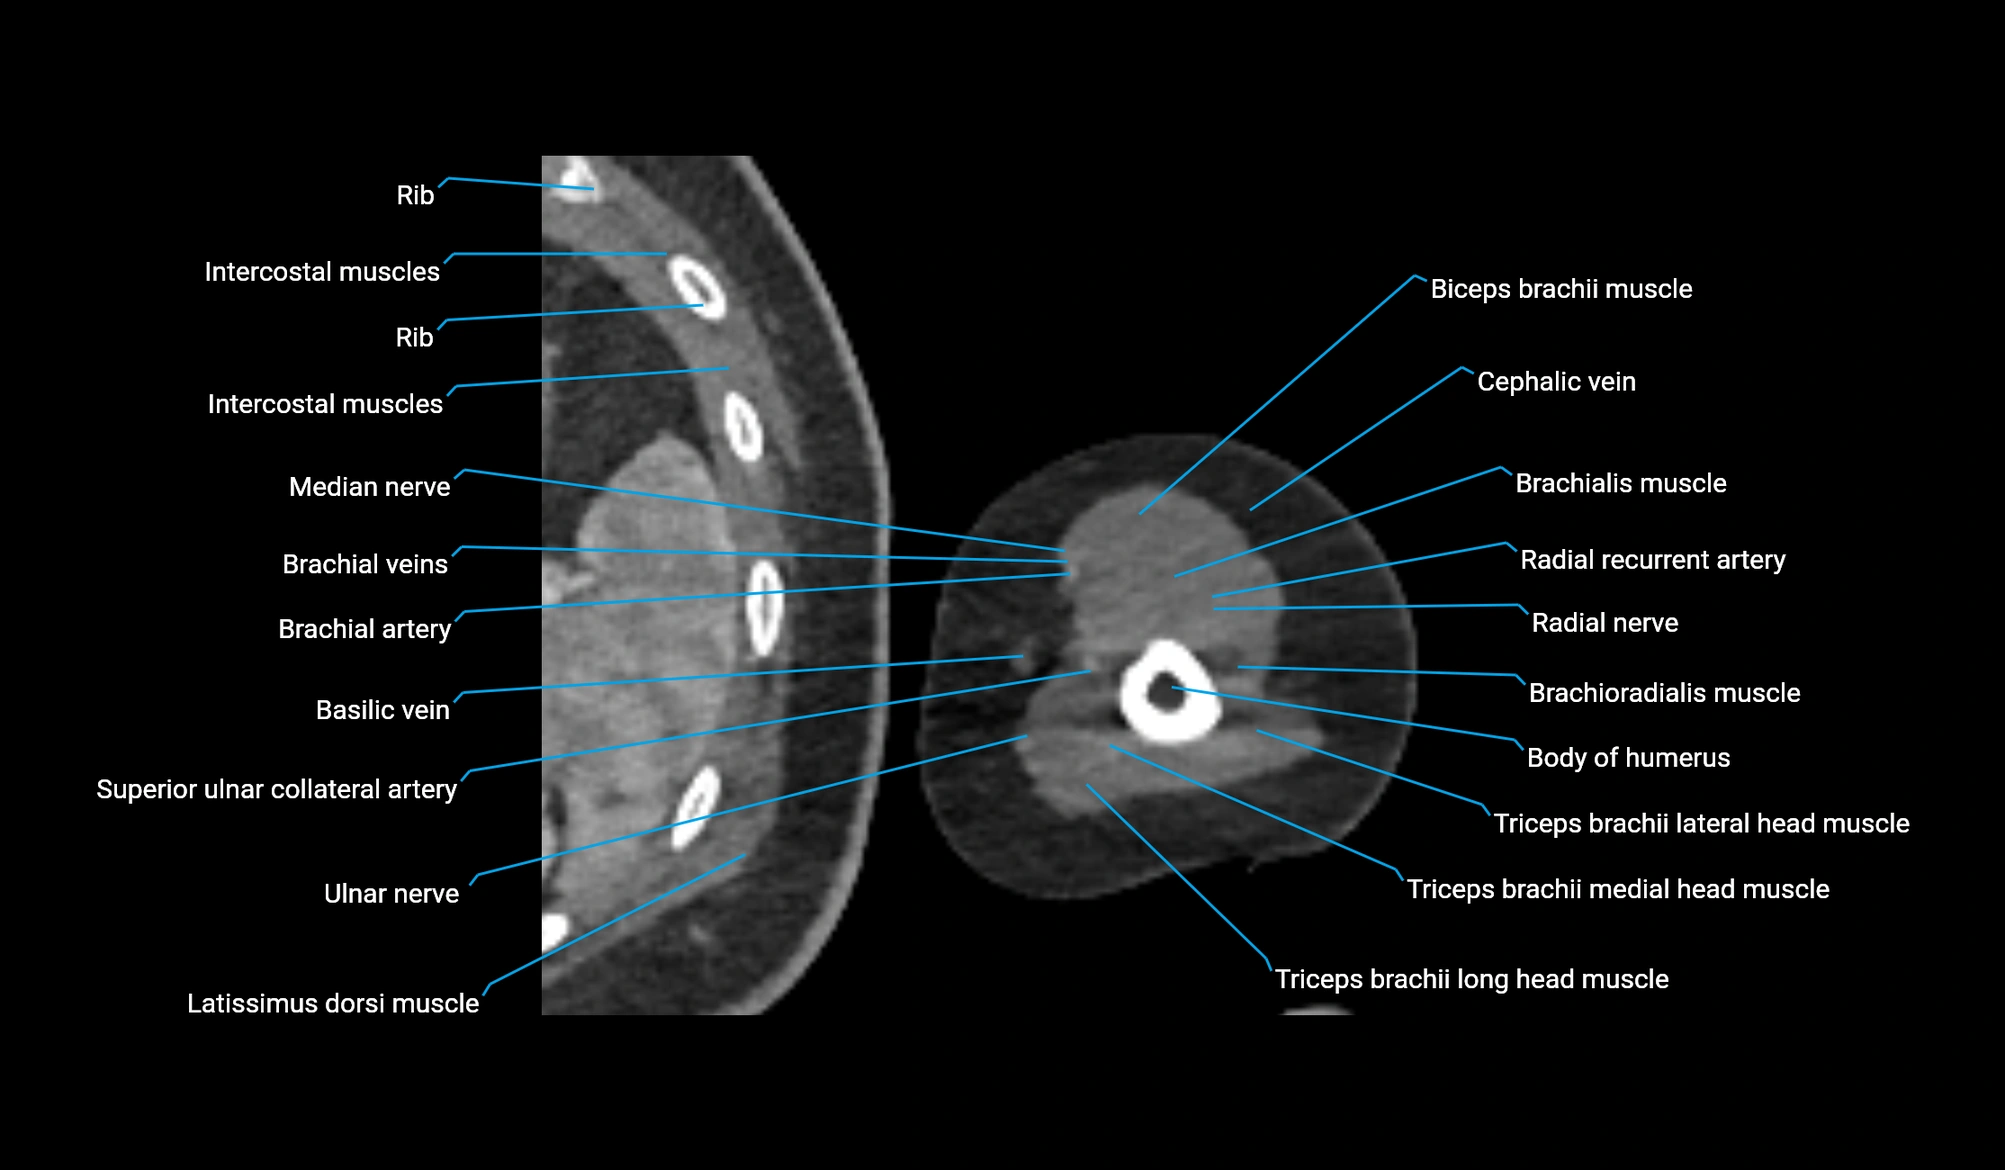

- Body of humerus

- Brachial artery

- Brachialis muscle

- Brachioradialis muscle

- Cephalic vein

- Long head of triceps brachii muscle

- Medial head of triceps brachii muscle

- Median nerve

- Radial nerve

- Radial recurrent artery

- Superior ulnar collateral artery

- Triceps brachii muscle

- Ulnar nerve